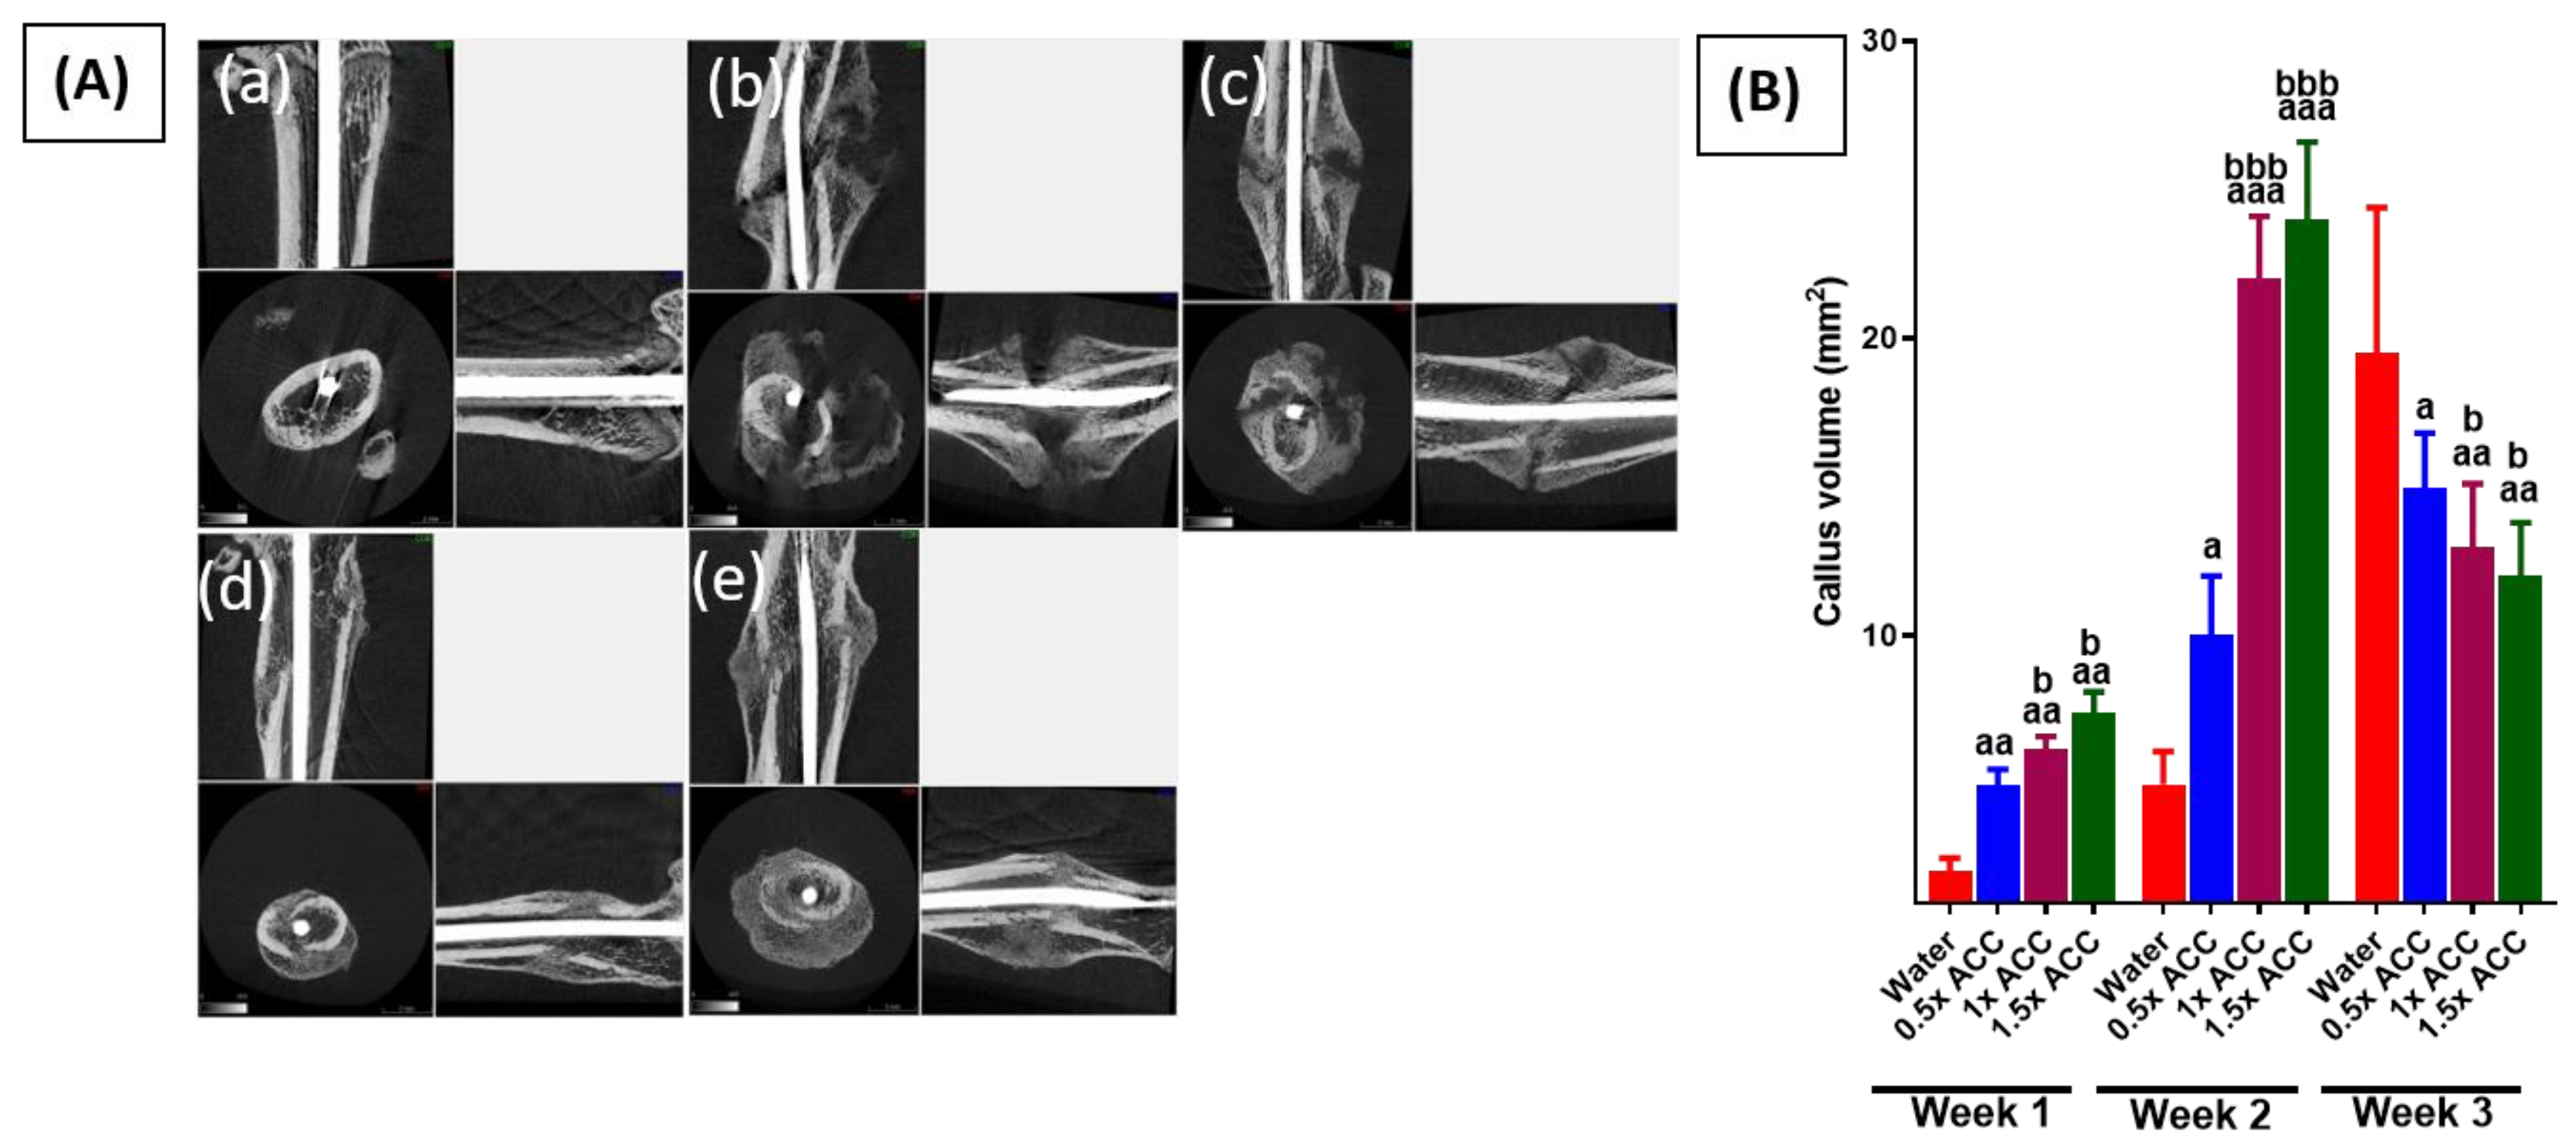

3.2. Radiological and Histomorphometry Results

3.3. Weight-Bearing Results